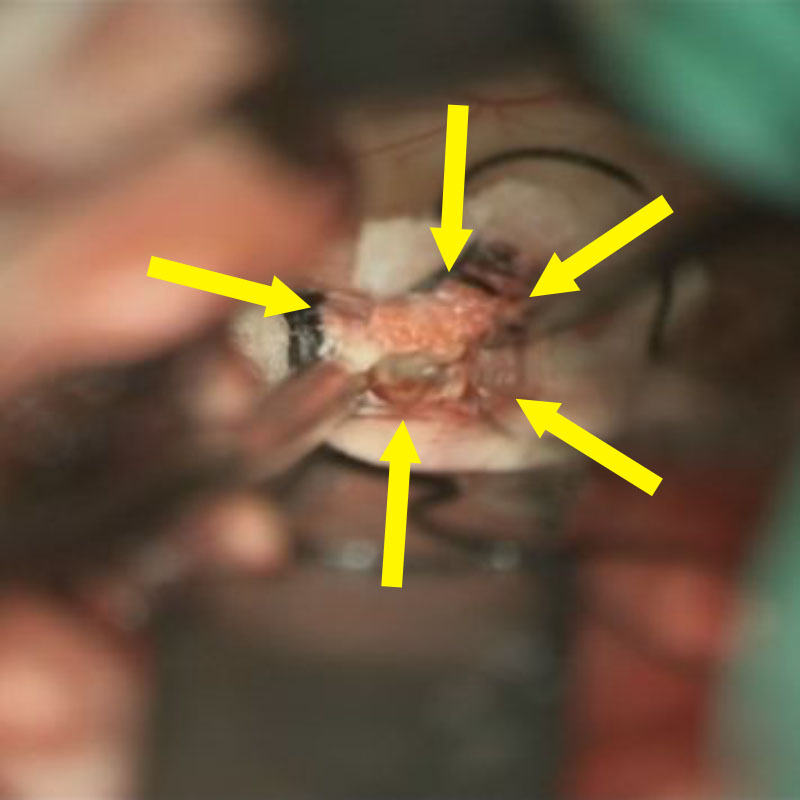

No.No.62 摘出前

No.No.62 摘出中1

No.No.62 摘出中2

No.No.62 摘出後

CT/MRにより完全に摘出されたことが確認された